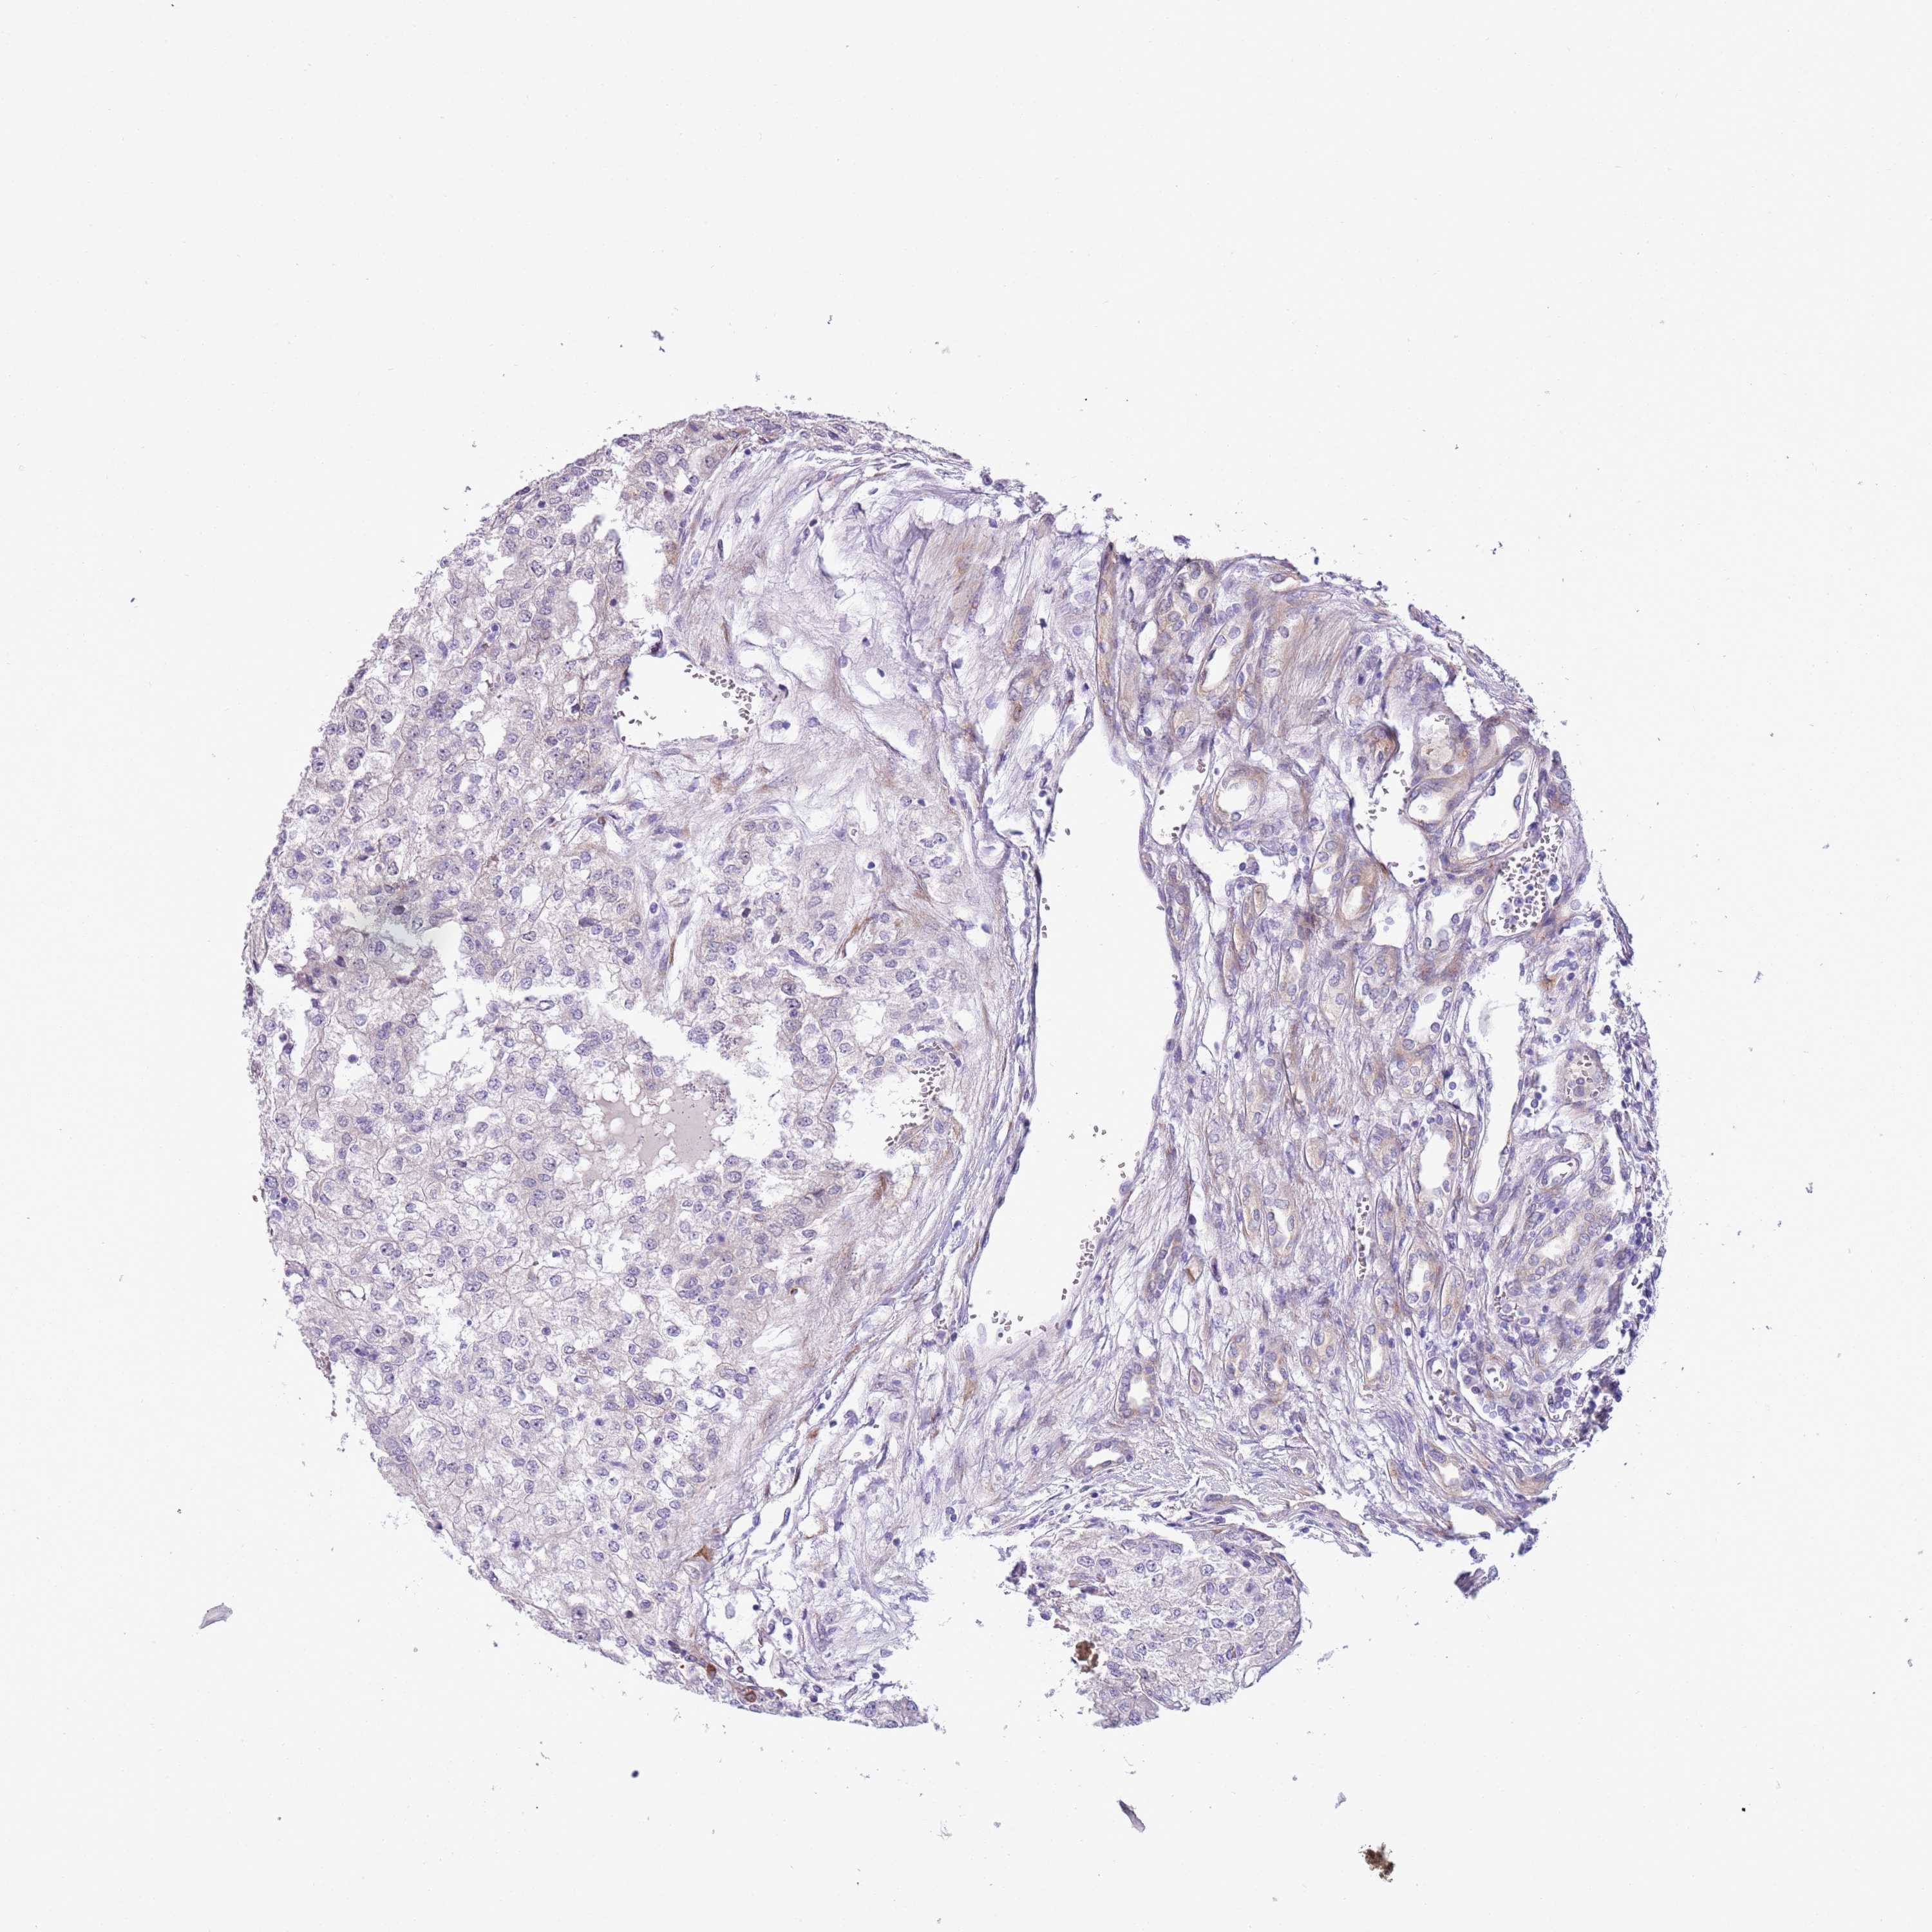

KIDNEY RENAL CLEAR CELL CARCINOMA (VALIDATION) - Interactive survival scatter ploti

The Survival Scatter plot shows the clinical status (i.e. dead or alive) for all individuals in the patient cohort, based on the same data that underlies the corresponding Kaplan-Meier plots. Patients that are alive at last time for follow-up are shown in blue and patients who have died during the study are shown in red.

The x-axis shows the expression levels (FPKM) of the investigated gene in the tumor tissue at the time of diagnosis. The y-axis shows the follow-up time after diagnosis (years). Both axes are complimented with kernel density curves demonstrating the data density over the axes. The top density plot shows the expression levels (FPKM) distribution among dead (red) and alive patients (blue). The right density plot shows the data density of the survived years of dead patients with high and low expression levels respectively, stratified using the cutoff indicated by the vertical dashed line through the Survival Scatter plot. This cutoff is automatically defined based on the FPKM cutoff that minimizes the p-score. The cutoff can be changed by dragging the vertical line or by entering a cutoff value in the square labeled "Current cut-off".

Under the Survival Scatter plot the p-score landscape (black curve; left axis) is shown together with dead median separation (red curve; right axis). Dead median separation is the difference in median mRNA expression between patients who have died with high and low expression, respectively. It is calculated as follows: median FPKM expression of dead patients with high expression - median FPKM expression of dead patients with low expression. This is intended to aid the user in visually exploring custom cutoffs and the associated p-scores and dead median separation.

Individual patient data is displayed and can be filtered by clicking on one or more of the category buttons on the top of the page. Categories describing expression level and patient information include: high, low, alive, dead, female, male and tumor stages. The scale of the x-axis can be toggled between linear and log-scale by clicking on the "x log" button. Mouse-over function shows TCGA ID, patient information and mRNA expression (FPKM) for each patient.

& Survival analysisi

Kaplan-Meier plots summarize results from analysis of correlation between mRNA expression level and patient survival. Patients were divided based on level of expression into one of the two groups "low" (under cut off) or "high" (over cut off). X-axis shows time for survival (years) and y-axis shows the probability of survival, where 1.0 corresponds to 100 percent.

MRPL32 is not prognostic in Kidney Renal Clear Cell Carcinoma (validation)

Best expression cut offi

Based on the FPKM value of each gene, patients were classified into two groups and association between prognosis (survival) and gene expression (FPKM) was examined. The best expression cut-off refers the FPKM value that yields maximal difference with regard to survival between the two groups at the lowest log-rank P-value. Best expression cut-off was selected based on survival analysis .

When clicking on this number, the vertical dashed line indicating cut-off, the interactive survival plot, and the Kaplan-Meier curve will be adjusted to show results based on the best expression cut-off.

: 64.1

P scorei

Log-rank P value for Kaplan-Meier plot showing results from analysis of correlation between mRNA expression level and patient survival.

N/A

5-year survival highi

5-year survival for patients with higher expression than the expression cutoff.

For melanoma and glioma, 3-year survival is shown.

5-year survival lowi

5-year survival for patients with lower expression than the expression cutoff.

TCGA RNA samplesi

RNA-seq data is reported as average FPKM (number Fragments Per Kilobase of exon per Million reads), generated by the The Cancer Genome Atlas (TCGA) .

Normal distribution across the dataset is visualized with box plots, shown as median and 25th and 75th percentiles. Points are displayed as outliers if they are above or below 1.5 times the interquartile range. FPKM values of the individual samples are presented next to the box plot.

Average pTPM 81.0

Number of samples 100